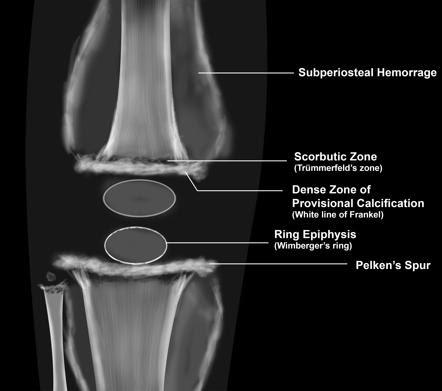

Wimberger Ring Sign

The Wimberger ring sign refers to a radiological finding characterized by a dense, sclerotic ring around the epiphysis of long bones, typically seen in cases of scurvy. This condition occurs due to subperiosteal hemorrhages and impaired collagen synthesis caused by vitamin C deficiency.

- Appearance: A sharply defined, dense, sclerotic ring surrounding the epiphysis.

- Cause: Reflects disorganized bone growth due to vitamin C deficiency.

- Associated Findings in Scurvy:

- Subperiosteal hemorrhages.

- Fragility fractures.

- “Corner sign” (a small metaphyseal fracture).

- “Trümmerfeld zone” or scorbutic zone (an area of lucency in the metaphysis).

- Generalized osteopenia.